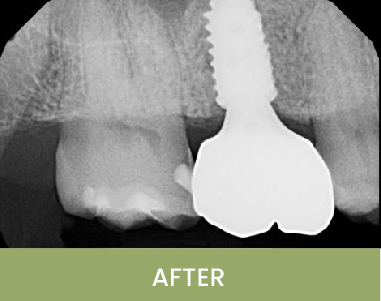

This patient had been missing upper left posterior teeth for an extended period. After careful evaluation and digital treatment planning, two implants were placed using a surgical guide in a minimally invasive manner. The implants were positioned with ideal spacing between each other and the adjacent teeth, providing the best outcome for long-term maintenance. The implants were restored three months later, giving the patient comfort and normal function once again.